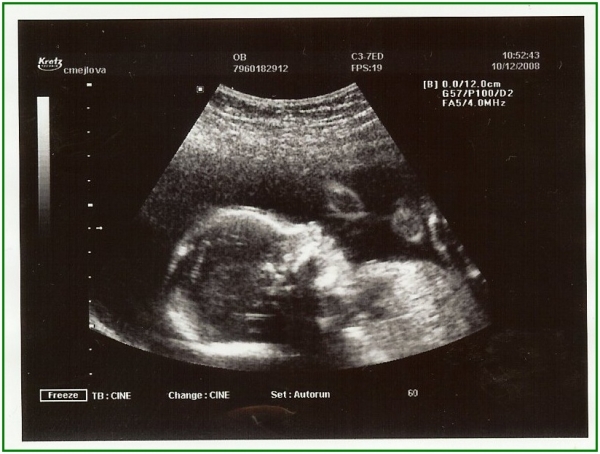

... další sledování aktivit. Lahvička se mrská jako blázen :-))) 15. dubna